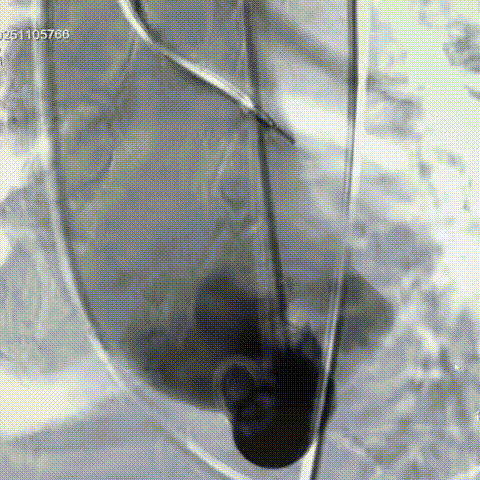

手术过程:在右股动脉穿刺建立通路后,顺利送入大鞘,经食道超声及血管造影确认路径稳定。18mm球囊预扩后评估冠脉灌注良好,后将Prostyle A® AV26瓣膜精准释放于目标位置,超声显示无瓣周漏,术后即刻造影显示无明显反流,术前PGmean40mmHg,术后导管测平均跨瓣压差8mmHg,心功能明显改善,患者生命体征平稳。

主动脉根部造影

定位

迅速锚定